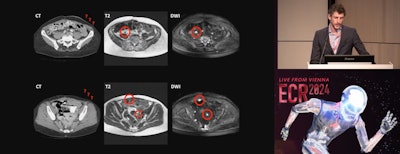

Research presented at ECR 2024 suggests that diffusion-weighted MRI (DW-MRI) has value in ovarian cancer treatment planning.

In his talk, Max Lahaye, MD, PhD, from the Netherlands Cancer Institute in Amsterdam discussed his team's findings which showed that DW-MRI could perform a complete primary and interval debulking with high accuracy.

Max Lahaye, MD, of the Netherlands Cancer Institute in Amsterdam presents findings on the clinical impact of dedicated MR staging of ovarian cancer patients during ECR 2024.

Although surgeons use a scoring system called a peritoneal cancer index (PCI) to divide the abdomen into 13 regions and measure the extent of disease, Lahaye's research showed that a special step in a surprise preoperative DW-MRI scan was especially useful.

"We have quite a simple MRI protocol: T2-weighted images, T1 pre- and postcontrast, and of course diffusion-weighted images," Lahaye said. "And I can't stress this enough: People have to drink one liter of pineapple juice because this will result in a nice quality because it will suppress the high signal on the diffusion-weighted images in the bowel. Because I don't want to see bowels, I want to see cancer. So please, use pineapple juice when you use these protocols."

"We as radiologists have a problem in depicting disease on CT, peritoneal disease. We have a sensitivity of 11% for lesions smaller than 5mm. That's really low. While on MRI, especially on diffusion-weighted images, these lesions light up like a lightbulb," he said.